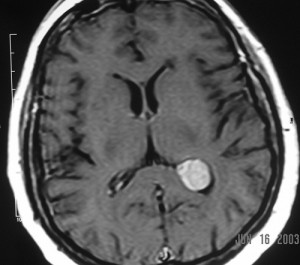

The images are a combination of T1 (before and after gadolinium enhancement), T2, and FLAIR pulse sequences in axial, sagittal and coronal sections of the patient’s brain (not all of the original images are in the monograph).

They reveal a 2cm mass in the trigone of the left lateral ventricle, centered within the choroid plexus. It has intermediate signal intensity on the pre-gadolinium T1WI, is hyperintense on the T2WI and enhances intensely and homogeneously after intravenous gadolinium administration. The mass is round, well-defined, has no mass-effects and does not invade the brain parenchyma. The ventricles are not dilated. The remainder of the brain is normal.